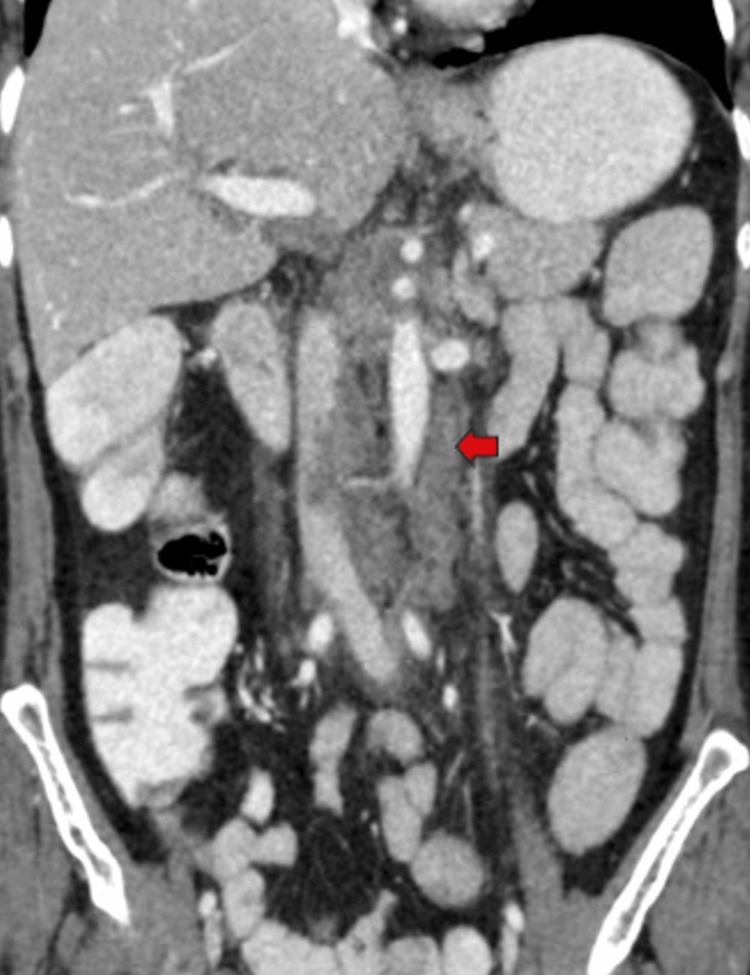

Furthermore, multiple lymph nodes of variable sizes, demonstrating mild heterogeneous post-contrast enhancement, were noted at the porta hepatis, peripancreatic region adjacent to the pancreatic head, celiac region, aorto-caval region, pre-aortic, and left para-aortic region, with the largest measuring approximately 18 x 35 mm (anteroposterior x transverse) at the porta hepatis (Figure 7). Both adrenal glands appeared normal, and there was no evidence of ascites. The rest of the abdominal organs exhibited normal appearances.

Multiple enlarged lymph nodes were noted at various locations, including the porta hepatis, peripancreatic region adjacent to the pancreatic head, celiac region, aorto-caval region, pre-aortic, left para-aortic region, and retrocaval region (Figure 11). These lymph nodes exhibited T1WI hypointensity and T2WI heterogeneous hyperintensity, with central necrotic areas of variable sizes. Some lymph nodes demonstrated diffusion restriction on DWI and appeared coalescent. The pancreas appeared normal. Visualized lower lobes of both lungs exhibited well-defined T2WI hyperintense lesions ranging in size from 2 to 15 mm, with peripheral and subpleural distribution.